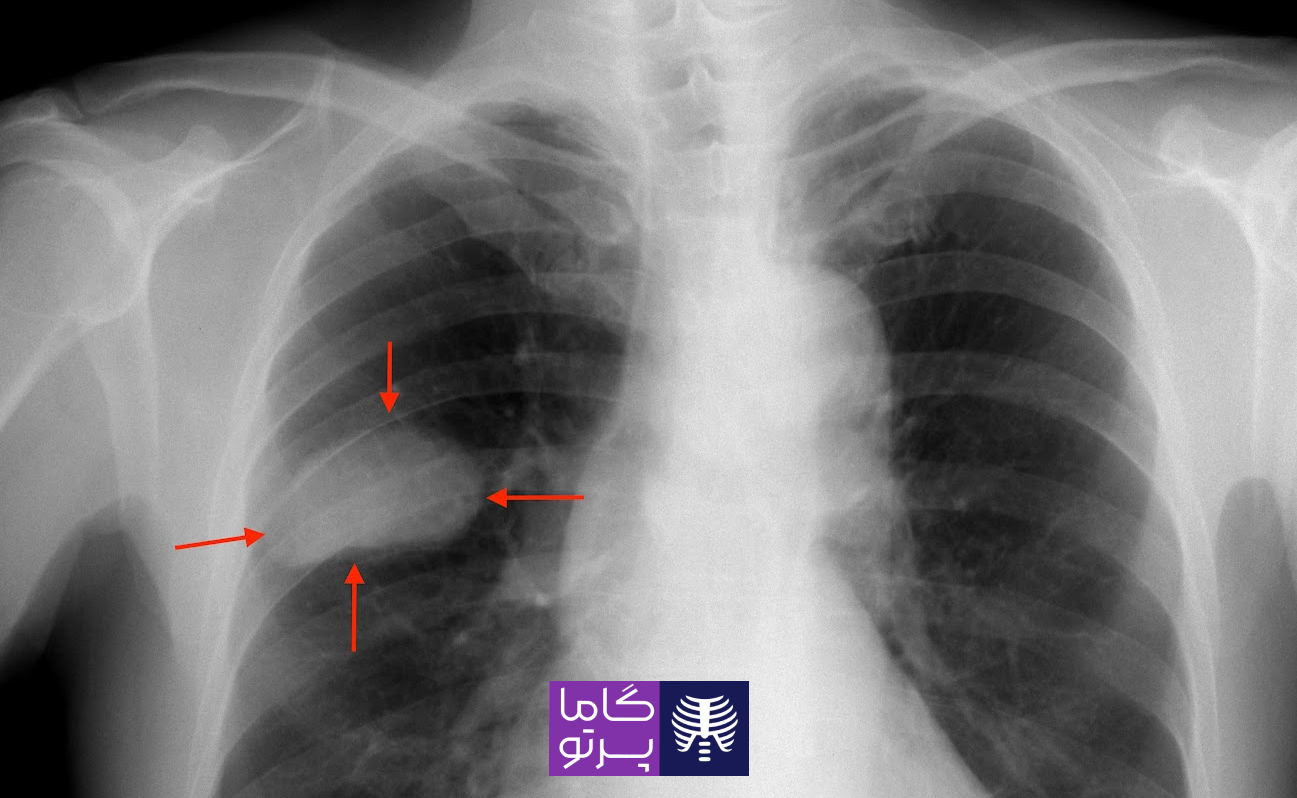

تصاویر زیر، نمونه کوچکی از راههایی را نشان می دهد که سرطان میتواند در عکس قفسه سینه ظاهر شود. آنها قرار است به شما نشان بدهند که سرطان ممکن

است به چه شکلی باشد تا بتوانید قبل از اینکه پزشک جزئیات تصاویر را به شما توضیح دهد، یک درک کلی داشته باشید.

انواع مختلفی از NSCLC وجود دارد که میتواند اندازه آنها متفاوت باشد و در نقاط مختلف ریه ظاهر شوند.

این نوع NSCLC اغلب در سطح خارجی ریهها قرار دارد. برای حدود نیمی از افراد مبتلا به آدنوکارسینوم، اشعه ایکس قفسه سینه نشان میدهد که تومور شروع به رشد درون بافتهای ریه یا سایر بافتهای واقع در وسط قفسه سینه، کرده است.

تومورهای سرطان سلول سنگفرشی، اغلب در وسط ریه یافت میشوند. بسیاری از تودههای سلول سنگفرشی دارای حفرههایی هستند، آنها حاوی یک یا چند حفره هوا هستند که ممکن است در عکسبرداری با اشعه ایکس بهعنوان یک لکه تاریک که توسط بافتی با رنگ روشنتر احاطه شده است، نشان داده شود.

یک بخش یا لوب ریه (بخش کوچکی از ریه) در بسیاری از افراد مبتلا به سرطان سلول سنگفرشی فرو میریزد. این بدان معنی است که هوا از ریه به فضای اطراف در قفسه سینه نشت میکند. از آنجایی که هوای کمتری وجود دارد، بخش یا لوب فرو ریخته ممکن است به صورت خاکستری روشنتر در عکس اشعه ایکس نشان داده شود.